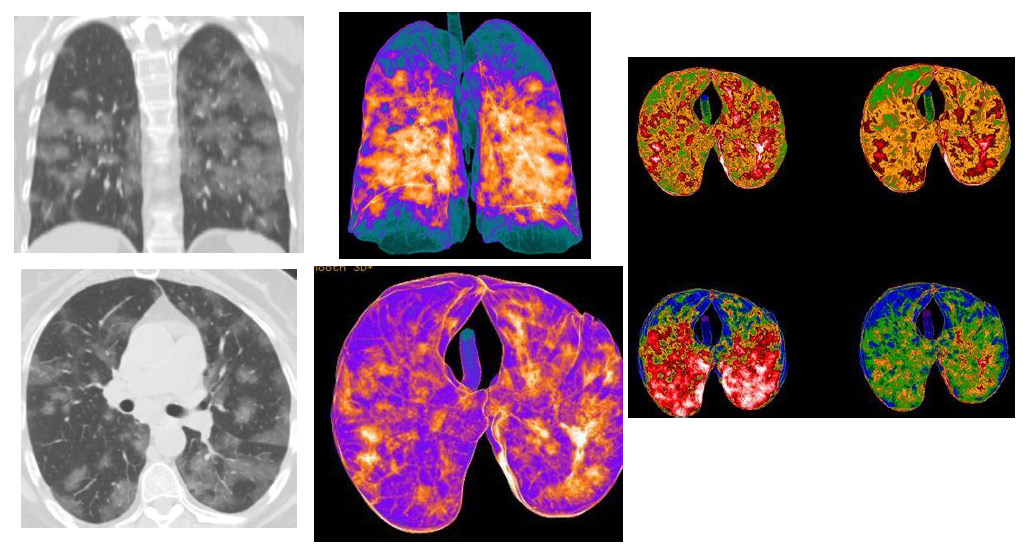

Figure 3: CT patterns of bilateral Covid-19 pneumonia of a 60-year-old female patient. MPR (coronal and axial) reconstructions showed: multiple bilateral consolidations areas, with bilateral interstitial thickenings, and few “ground-glass” areas. In the Volume Rendering (VRT) “colored” reconstructions (three images), the blue/green areas represented the normal lung parenchyma (also in the ventral and dorsal areas), while orange/ white and red areas indicate the inflammatory pulmonary involvements, with consolidations.